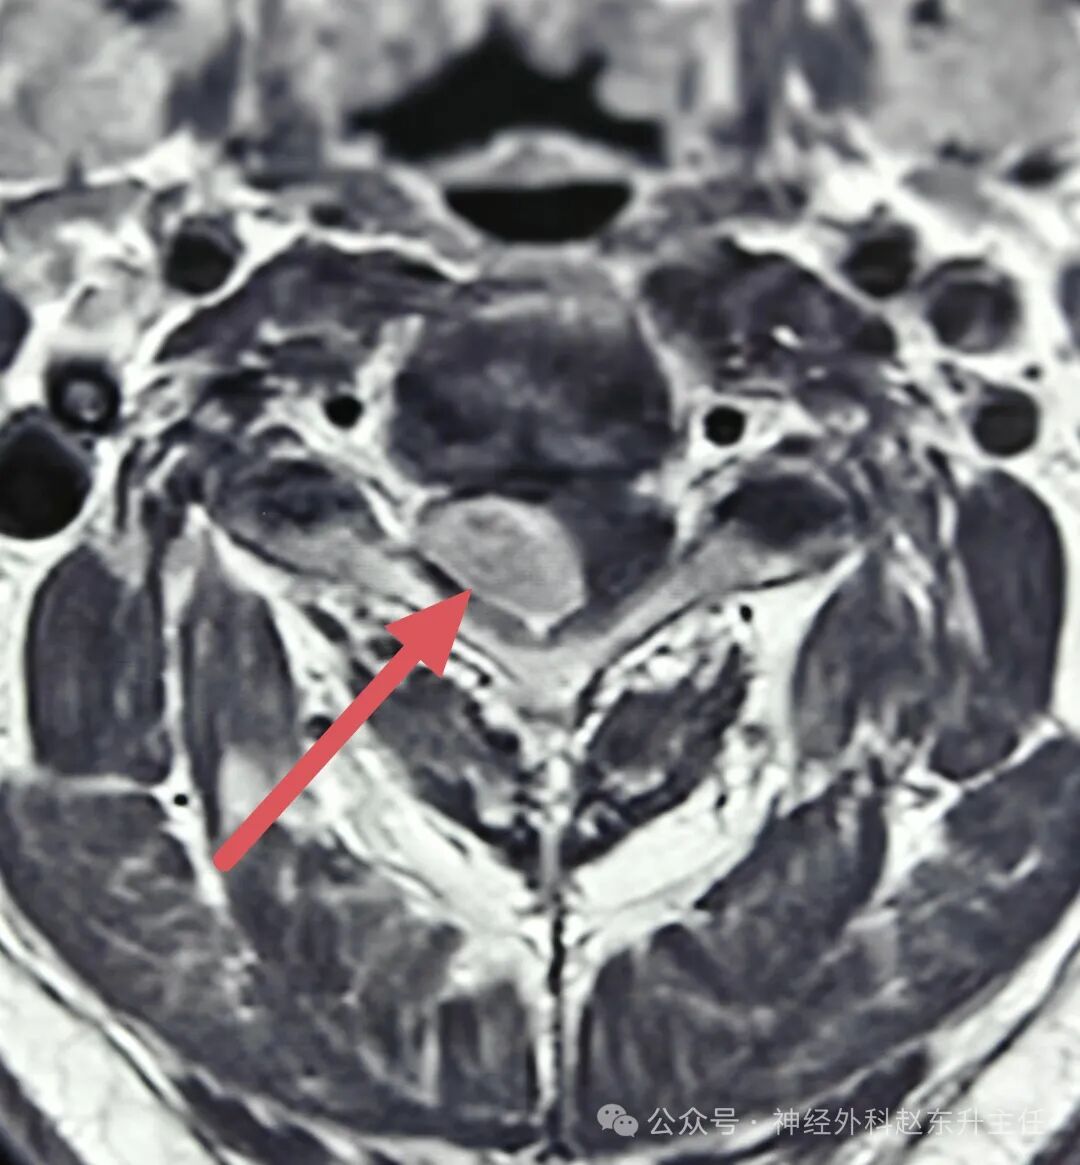

姚先生4月前感觉双手麻木,右手较明显,且持续加重,无颈肩部及上肢疼痛,在当地医院查颈椎MRI提示颈3-4椎管内肿瘤,肿瘤将近2cm大小,严重压迫脊髓。患者本身合并高血压,最高达170/105mmHg,看到这个结果,患者非常担心,随后找到西安市红会医院神经外科赵东升主任,赵主任看过片子后认为患者椎管内肿瘤为良性,手术可一次性治愈,建议手术治疗,家属在反复思想斗争下决定让赵主任主导手术。

IMG_20250530_155434.jpgIMG_20250530_155452.jpgIMG_20250530_155409.jpg术前磁共振增强显示肿瘤较大,质地较硬,压迫脊髓明显

手术在全麻下进行,使用高倍显微镜仔细剥离肿瘤,术中电生理监测,未损伤神经,并且将肿瘤完全切除。术后病理提示为神经鞘瘤。